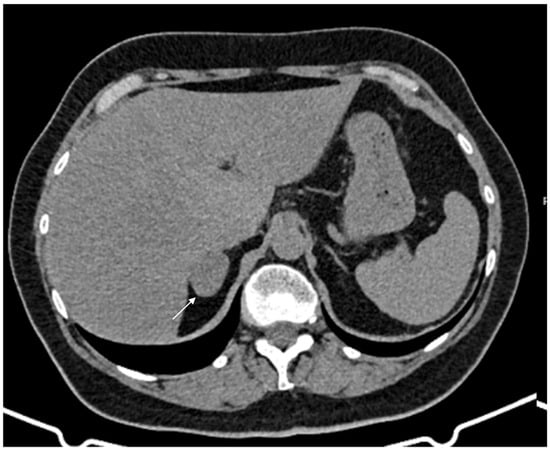

Figure 1.

60-year-old woman with adrenal adenoma. Accidental CT finding of a right adrenal mass (arrow) of approximately 3 cm, homogeneous with clear margins and density values lower than 10 HU.